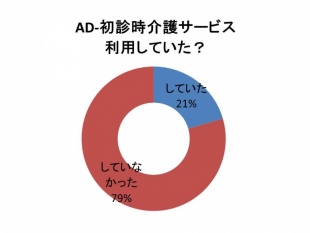

Q 認知症の人は介護サービスを利用した方がよいですか?

認知症の治療は薬だけでは限界があります。薬と同時に介護サービスを利用するなどの刺激が必要です。認知症のある方は、1日「自宅でじっとテレビを見て過ごしている」とか「寝ていることが多い」ようです。当院に認知症で受診された方の約8割が、受診時に介護サービスを利用されておりませんでした。認知症の予防目的で介護サービスの利用が勧められます。